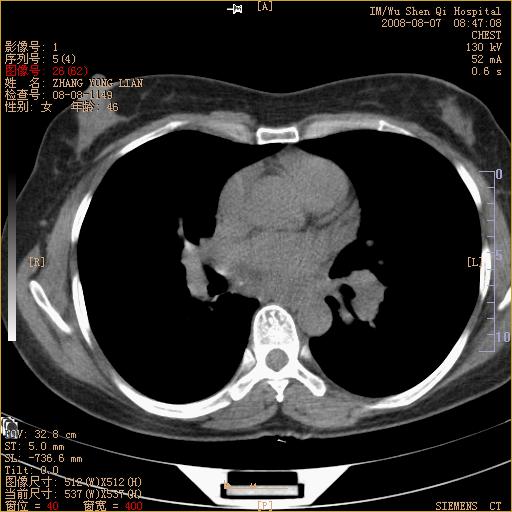

标题: CT15050:女,46岁,咳嗽胸痛一月余 [打印本页]

纵隔窗没发全,左下肺近胸膜处结节。有长毛刺,纵隔淋巴结增大,不排除恶性病变。

考虑肺癌

考虑左肺下叶后基底段周围型肺癌伴纵隔淋巴结转移可能性大。

左下肺ca并纵隔及左肺门区淋巴结转移。

脾脏低密度结节转移不排除。

1)考虑左肺下叶后基底段周围型肺癌伴纵隔淋巴结转移。2)脾内低密度灶,性质待定;不排除转移瘤可能。